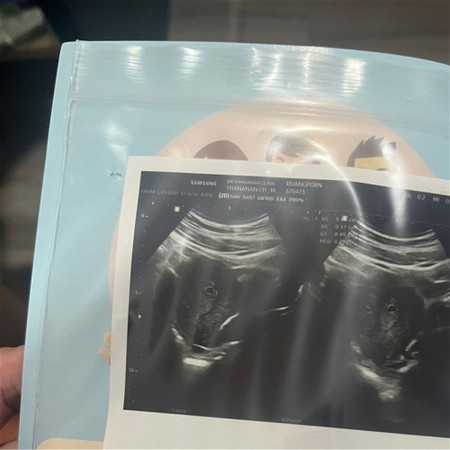

เจอแต่ถุงตั้งครรภ์

เราจำรอบเดือนครั้งสุดท้ายไม่ได้ แต่เท่าที่จำได้คือประมาณ15 เมษายนค่ะ 5 มิถุนายนตรวจเจอสองขีด วันที่6ไปฝากท้อง หมอซาวด์เจอถุงลมขนาด4 มิลค่ะ แต่ยังไม่เจอตัวอ่อน แบบนี้ปกติไหมคะ วันที่20 นี้นัดอีกรอบค่ะค่ะ

ปกติจ้า น่าจะราวๆ4-5วีค